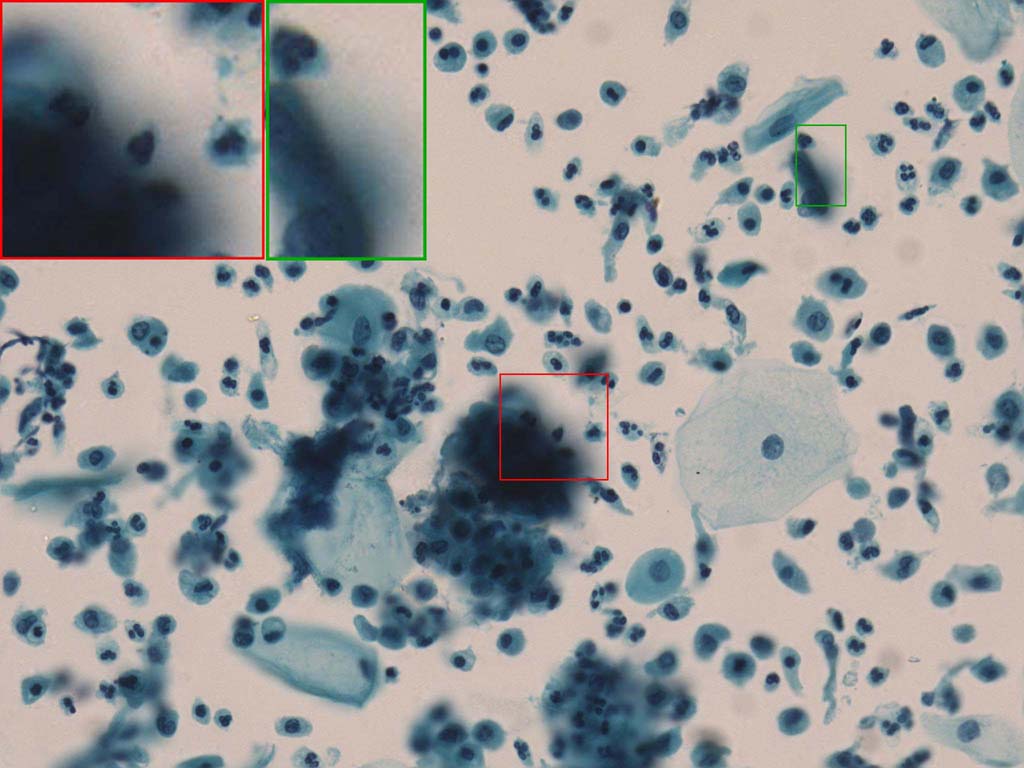

To demonstrate the effectiveness and efficiency of the proposed image fusion method , we conduct a set of comparative experiments on three image datasets. The first is composed by 8 pairs of multi-modal medical images and the second one contains 15 pairs of multi-focus gray or color natural images. These two datasets are often used in many related papers and some examples are shown in Figure 3(a) and Figure 3(b). The third one is a new multi-focus cervical cell image dataset collected by ourselves, which consists of 15 groups of color images and each group contains a series of multi-focus cervix cell images with size of or , etc. Some source examples are shown in Figure 3(c). Our source code implemented in C++ along with the new multi-focus cervical cell image dataset is available online.

Figure 9, Figure 10 and Figure 11 show the comparative fused results of the multi-focus cell images shown in Figure 3(c). For clarity, we also present a closeup view in the right-bottom of each sub-picture in Figure 9 and Figure 10. As shown in the close-up views of Figure 9, the fused images based on DSIFT, IM, MWGF and BF methods are extremely blurred in the boundary and fail to keep the details of cell nucleus. Furthermore, the DTCWT and NSCT based methods produce halo artifacts in the fused images, while GFF and CNN based methods fail to preserve the small cell nucleus. LP-SR based method nearly works fine which keeps the most of the details of the small size cells, but the integrity of the clustered large size cells is damaged. Fortunately, in our proposed method, the integrity of the clustered large size cells is preserved and most of the isolated small size cells are maintained from the original images, which demonstrates the best visual quality.

Similarly, as shown in the close-up views of Figure 10, the fused images from DSIFT, IM, MWGF and BF are blurred and lose some nucleus details, while the results from DTCWT, GFF, CNN and NSCT produce halo artifacts. LP-SR based method can keep details well but also produces halo artifacts and other noise. Our method can preserve the focused areas of different source images well without introducing any artifacts. For the example illustrated in Figure 11, the fused images generated by DSIFT, DTCWT, IM and NSCT all fail to preserve the focused areas of different source images and result in extremely blurred images. The GFF, CNN, MWGF and BF based method introduces a lot of color distortion of the nucleus regions and the obvious halo artifact. The result of LP-SR based method is close to the one of our method but introduces some odd color distortion. Again, our method produces fused image which can preserve the focused areas of different source images well without introducing any artifacts.